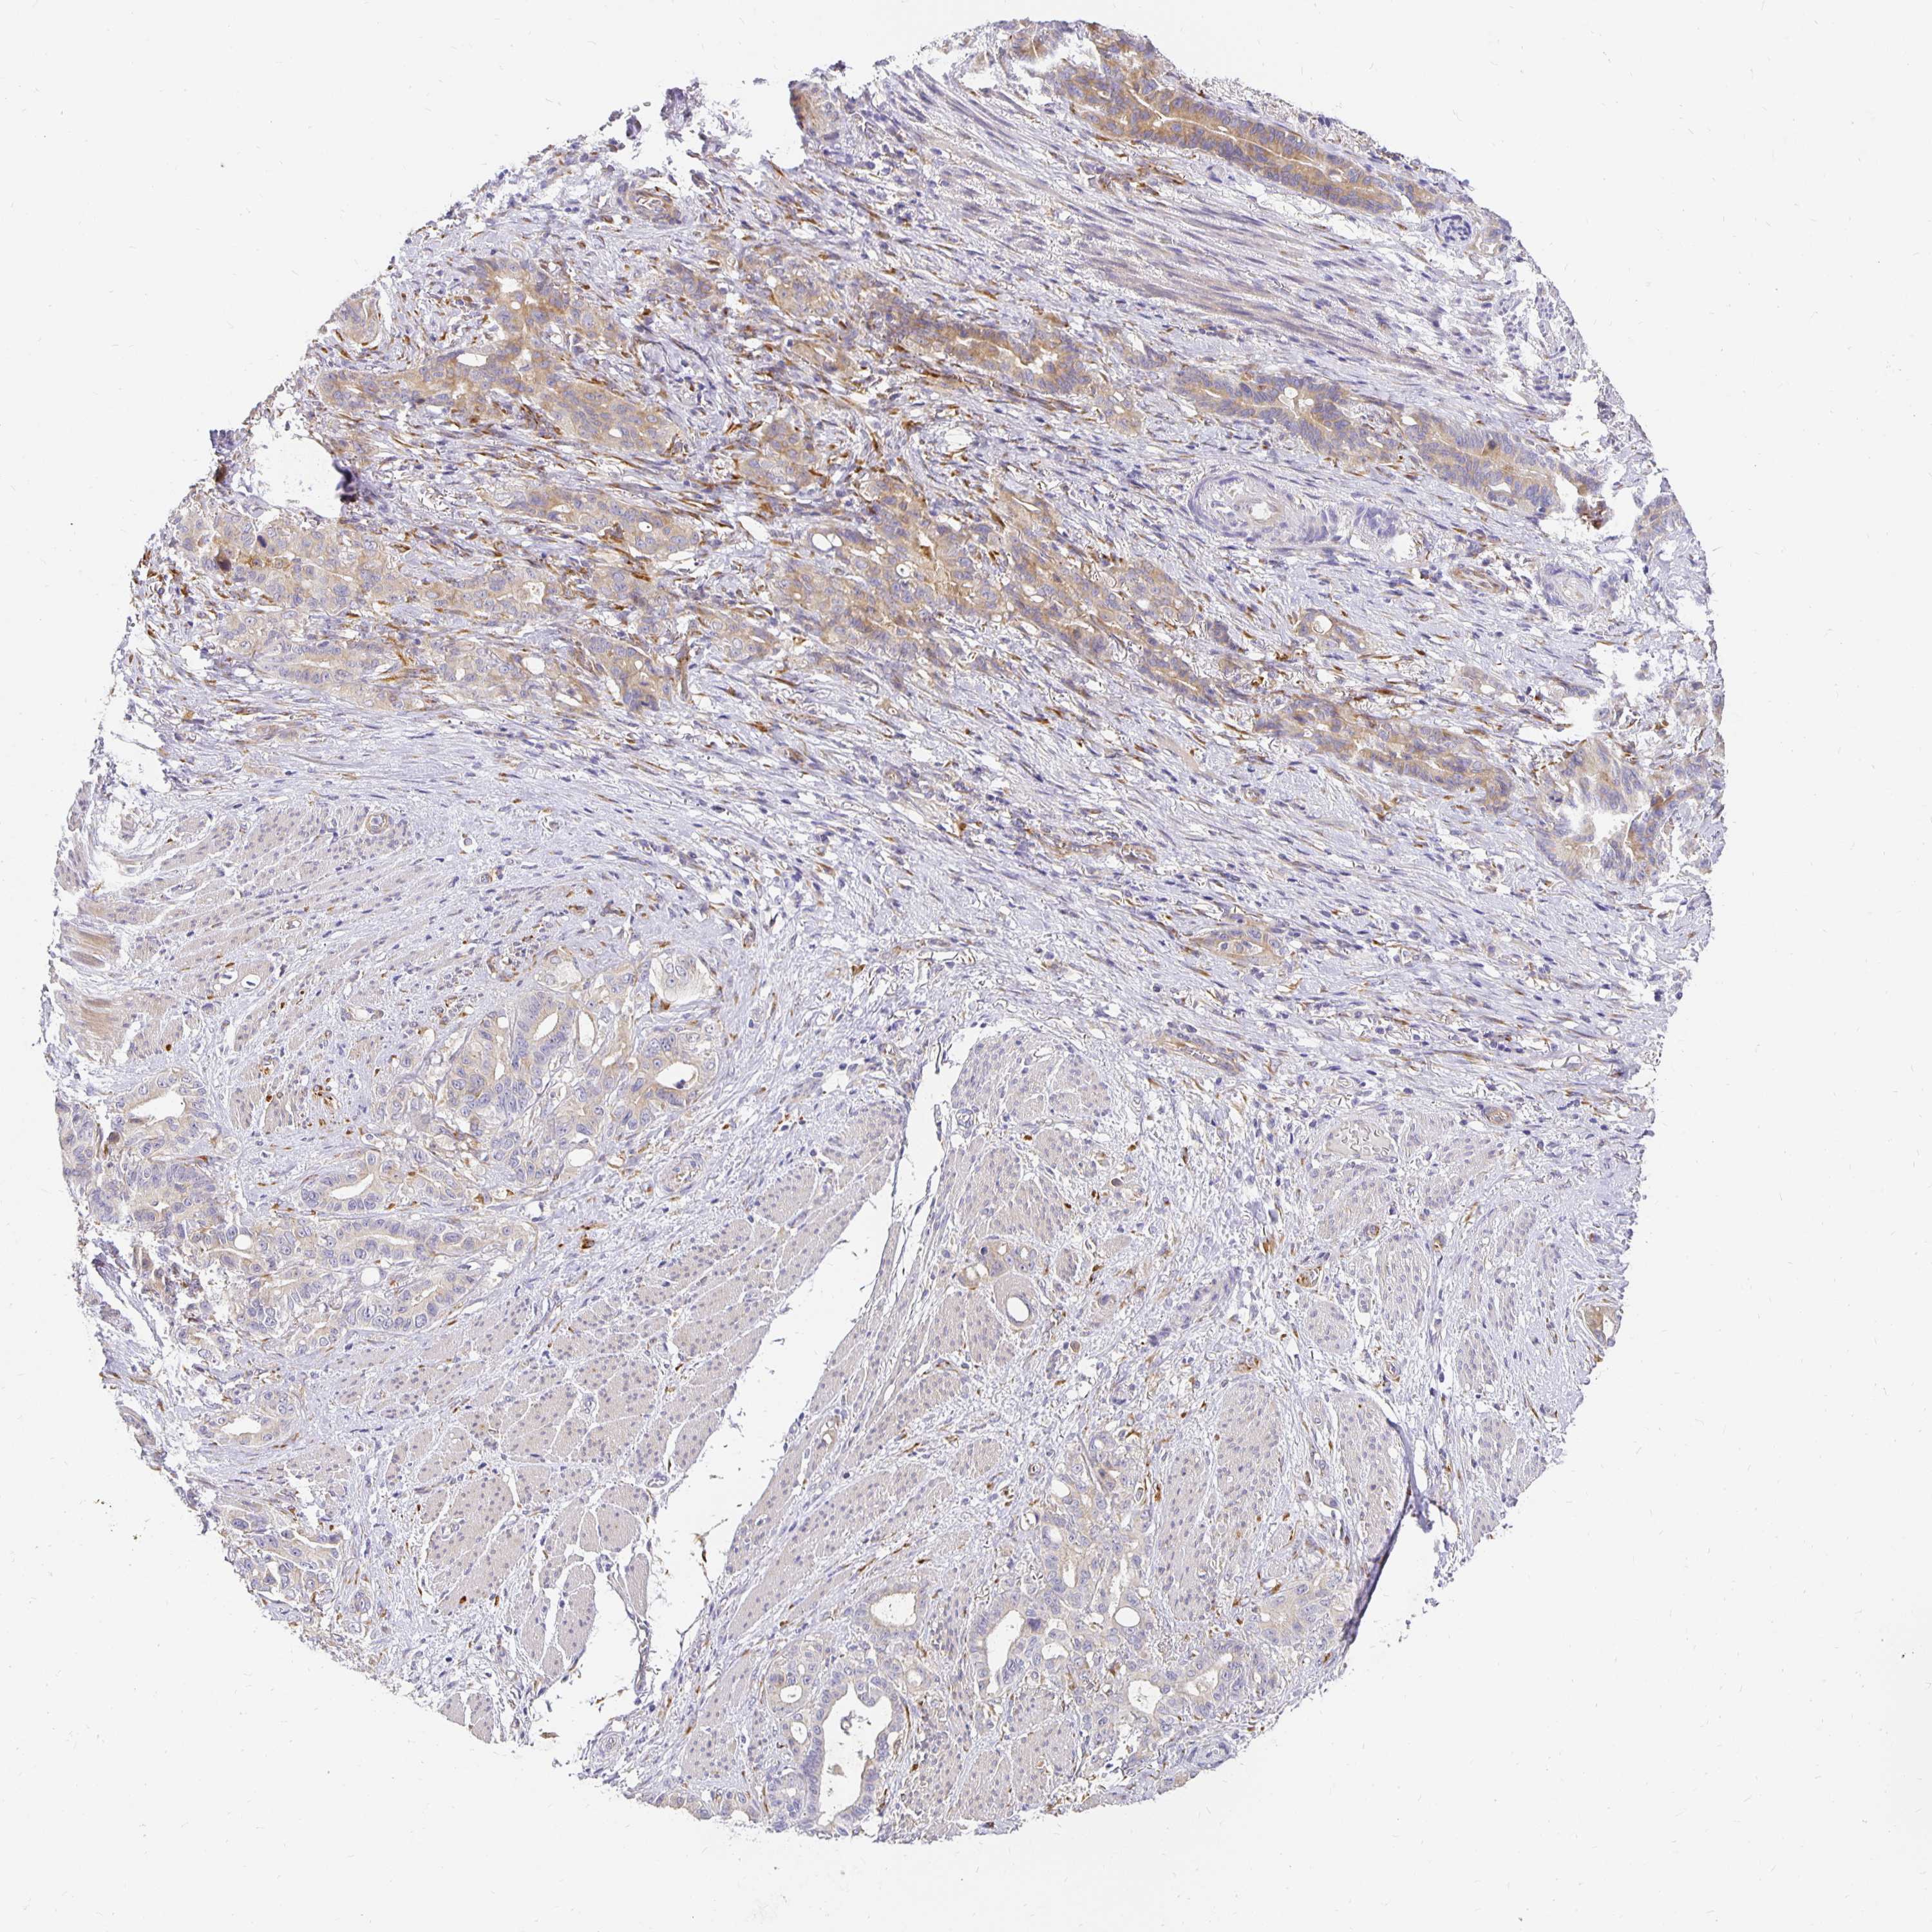

STOMACH CANCER - Protein expressioni

A mouse-over function shows sample information and annotation data. Click on an image to view it in a full screen mode. Samples can be filtered based on level of antibody staining by selecting one or several of the following categories: high, medium, low and not detected. The assay and annotation is described here.

Note that samples used for immunohistochemistry by the Human Protein Atlas do not correspond to samples in the TCGA dataset.

Antibody stainingi

Antibody staining in the annotated cell types in the current human tissue is reported as not detected, low, medium, or high, based on conventional immunohistochemistry profiling in selected tissues. This score is based on the combination of the staining intensity and fraction of stained cells.

Each image is clickable and will lead to virtual microscopy that enables deeper exploration of all samples and also displays staining intensity scores, fraction scores and subcellular localization as well as patient and tissue information for each sample.

Antibody HPA049137

Antibody HPA055799

Staining

High

Medium

Low

Not detected

Intensity

Strong

Moderate

Weak

Negative

Quantity

>75%

75%-25%

<25%

None

Location

Nuclear

Cytoplasmic/membranous

Cytoplasmic/membranous,nuclear

Adenocarcinoma, NOS